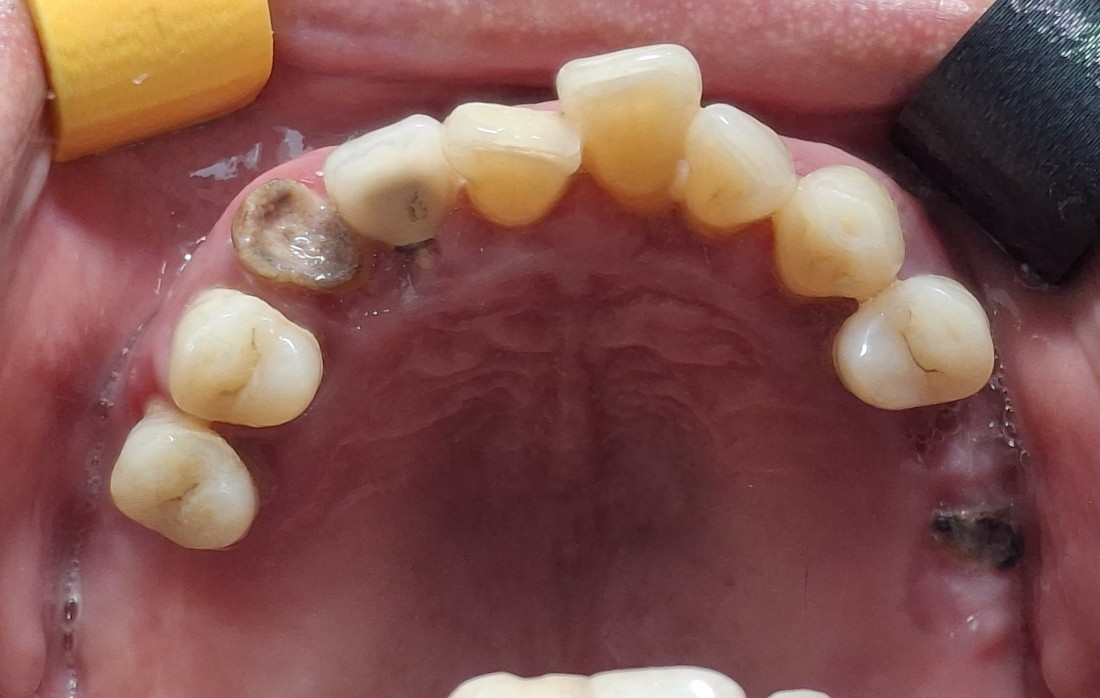

광주 전체임플란트

치료 케이스가 많은 치과가

잘하는 치과입니다.

광주 전체임플란트 케이스만

수 백가지로 정리하여

위의 홈페이지에 올려드리고 있는데요.

치과의사도 경험이 풍부한 사람이

여러 케이스를 다 다뤄보았기 때문에

좋은 임플란트 실력을 믿을 수 있습니다.